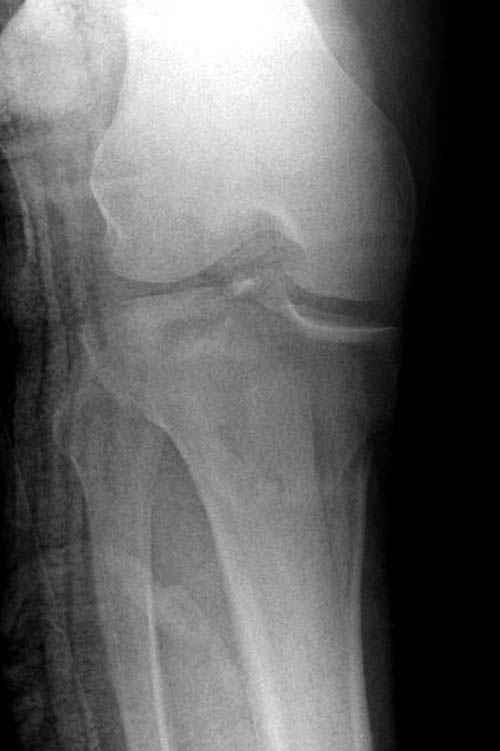

Трудно поверить, что разрекламированная Ортопедическая школа Восточной Украины позволяет такие странные снимки? На прямом снимке сохранен общий контур плато, но не известна судьба импрессии суставной поверхности. На полубоковой?, оставлен без репозиции задне-медиальный отдел, и навряд ли после такой фиксации можно удовлетвориться результатом.

На представленных предоперационных срезах КТ огромный задне-медиальный фрагмент расположен больше кзади, чем медиально. Для планирования, кроме поперечных срезов, надо ориентироваться на корональные срезы, которые укажут топографию верхушки медиального фрагмента.

При сложных переломах тибиал плато для своего рода Damage Control мы иногда применяем поэтапную тактику. Сперва оперируется одна сторона, а потом после рекондиции мягких тканей окончательный этап.

Если состояние мягких тканей позволяет, я бы предложил такой метод для вашего больного. Без предварительного планирования будет трудно, но шанс не надо упускать. Всего несколько дней после операции, и такая тактика лучше, чем недовольный молодой пациент.

Доступ к медиальной стороне задний или медиальный, через pes или в пространстве между medial gastroc мышцы.

Надеюсь, представленные снимки разных случаев помогут разобраться в тактике, и критика примется без личной обиды.